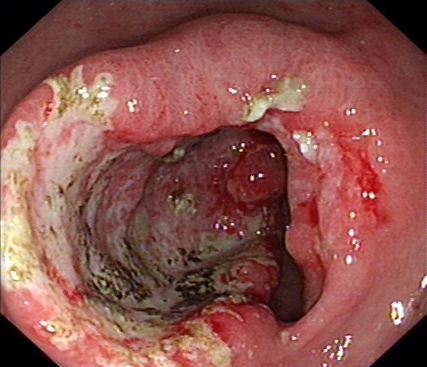

我们再来看一组胃镜图片,由胃溃疡到胃癌的过程(图片来源于网络)。患者未按医生医嘱,定期复查胃镜活检,最后进展为晚期胃癌。